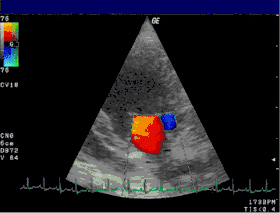

Severe MR Legend

1 Left atrium (LA) – 2 MR Jet, LV Left ventricle – RV Right ventricle – RA Right atrium

An echocardiogram is commonly used to confirm the diagnosis of MR.[16] Color doppler flow on the transthoracic echocardiogram (TTE) will reveal a jet of blood flowing from the left ventricle into the left atrium during ventricular systole. Also, it may detect a dilated left atrium and ventricle and decreased left ventricular function.[6] A transesophageal echocardiogram can give clearer images if needed as the back of the heart can also be viewed.[17]